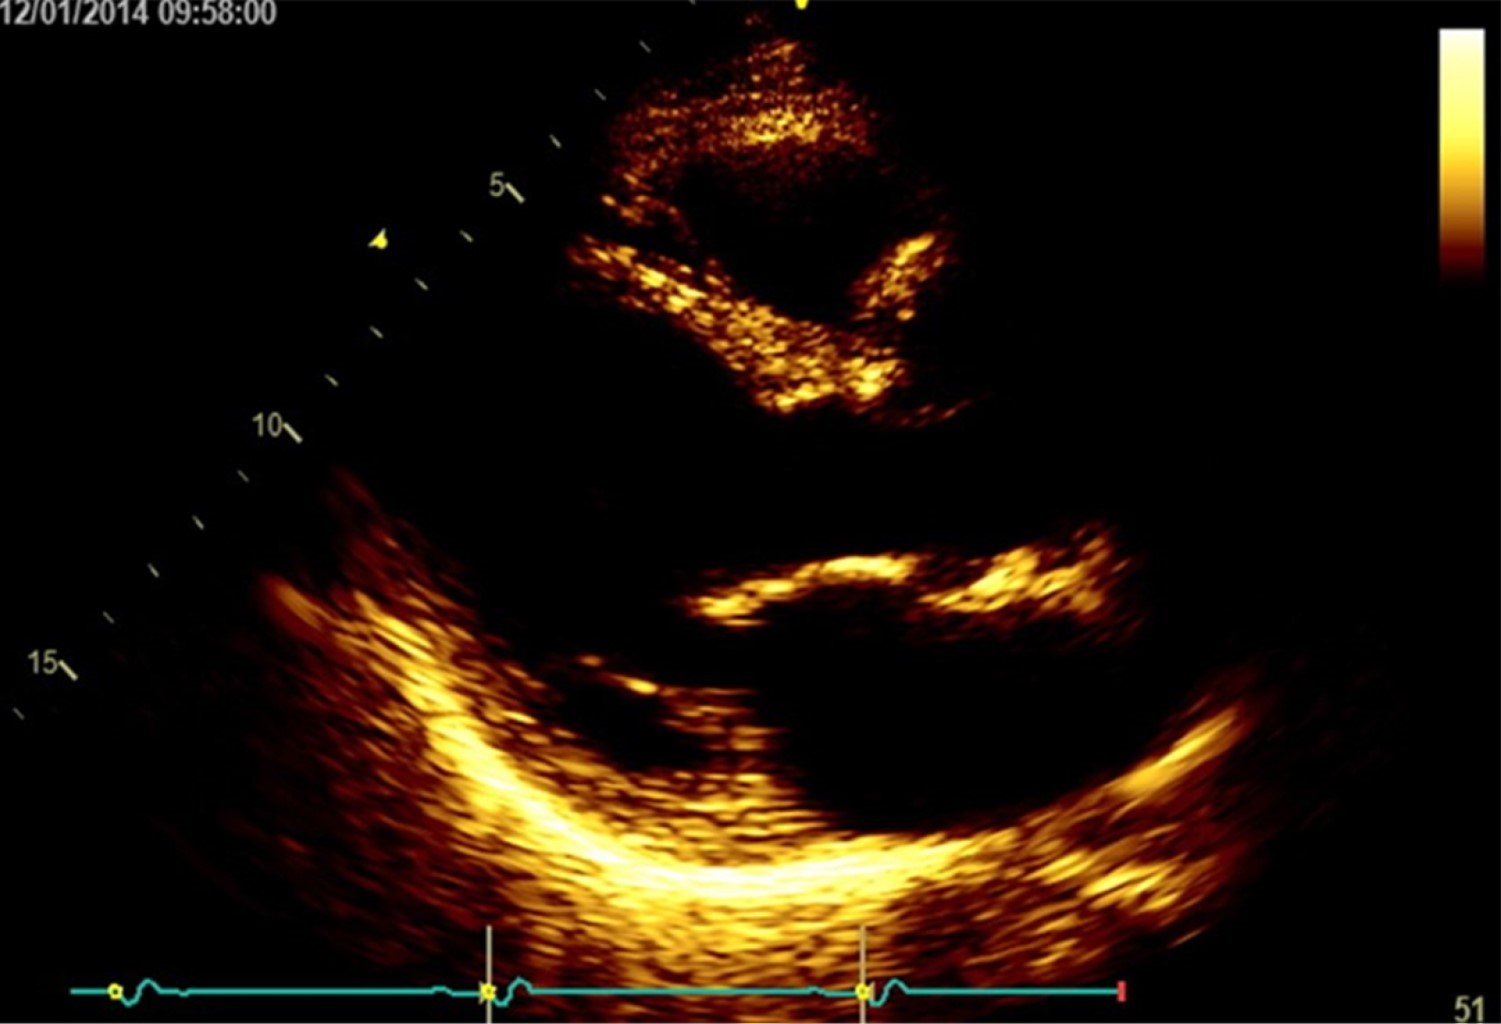

''Una bota en el corazón''. Reporte de un caso de seno de Valsalva no roto de forma particular y revisión de la literatura

Los aneurismas del seno de Valsalva son dilataciones congénitas o adquiridas de la pared del seno aórtico a nivel justo por encima de las tres cúspides de la válvula aórtica, que pueden ser casos asintomáticos o fatales si se rompen, más frecuentemente hacia las cavidades cardiacas derechas. Estos casos son relativamente raros. Presentamos el caso de un varón de 72 años remitido por sospecha de soplo pulmonar. La evaluación reveló un aneurisma del seno de Valsalva derecho, que causaba compresión del tracto de salida del ventrículo derecho (TSVD). El ecocardiograma, la tomografía computarizada y el aortograma revelaron imágenes interesantes y evocadoras. El paciente recibió una reparación quirúrgica mid-cap. Este artículo revisa y discute la literatura actual y presenta el caso.

Figura 1

Figura 2

Figura 3

Figura 4

Figura 5